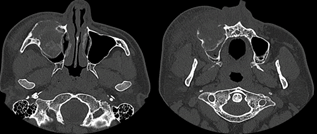

The remaining medical history was without clinical significance. At that time, the patient had not undergone any diagnostic imaging examinations. Therefore, a complete preoperative imaging diagnosis was performed, starting with cone beam CT (CBCT) and then regular computed tomography of the head and neck with emphasis on the maxillofacial region to assess the extent of the lesion and the potential infiltration of adjacent structures, including the skull bones and soft tissue (Figures 2 and 3).

Journal-Neurological-Disorders-Bony

Figure 2. CT images: Bony window, axial section. A 34 year old male patient before surgical intervention had a mass-like lesion with interruption of the anterior wall of the right maxillary sinus and swelling and deformity of the soft tissues in the right cheek and buccal region.

Head and neck CT was performed on a multidetector scanner (80 detector rows and 160 layers Aquilion Prime CT scanner) with a layer thickness of 0.5 mm in 2D axial plane images, and 3D and MIP reconstructions were made. The iodine contrast was injected into the cubital vein with an automatic syringe according to the scheme of the adopted protocol. The image data were stored as DICOM files. The first preoperative CT examination showed an extended and expansile, inhomogeneous tumorlike mass growing from the anterior maxillary wall almost completely filling the right maxillary sinus, partly sclerotic and calcified with some ground glass appearance. The only narrow line of air was visible near the posterior wall of the maxillary sinus. The dimensions of the heterogeneous tumor-like mass with polymorphic calcifications were approximately 50 mm × 36 mm × 53 mm. The tumor modeled and thinned the roof of the right maxillary sinus and curved toward the right orbit and eye, including the infraorbital canal. However, there was no pathological mass enlargement or invasion of the orbit, extra or intraconal tissue, eyeball or optic nerve. The lesion was an expanding infiltrating type of hyperplasia that caused bulging and reached the bony cortex, mostly the anterior wall of the maxillary sinus, with its local rupture. The loss of an approximately 25 mm cortical layer in the lower part of the anterior wall was noticed, with some invasion and penetration into the soft tissues of the cheek. The radiological CT images were ambiguous and locally had the features of an aggressive, malignant lesion or its malignant transformation (Figures 2 and 3). Therefore, it was decided to execute a punch biopsy under local anesthesia for histopathological analysis. Finally, the pathological examination revealed fibrous dysplasia. No pathological or enlarged lymph nodes of the head and neck region were noticed on the CT or US examination.